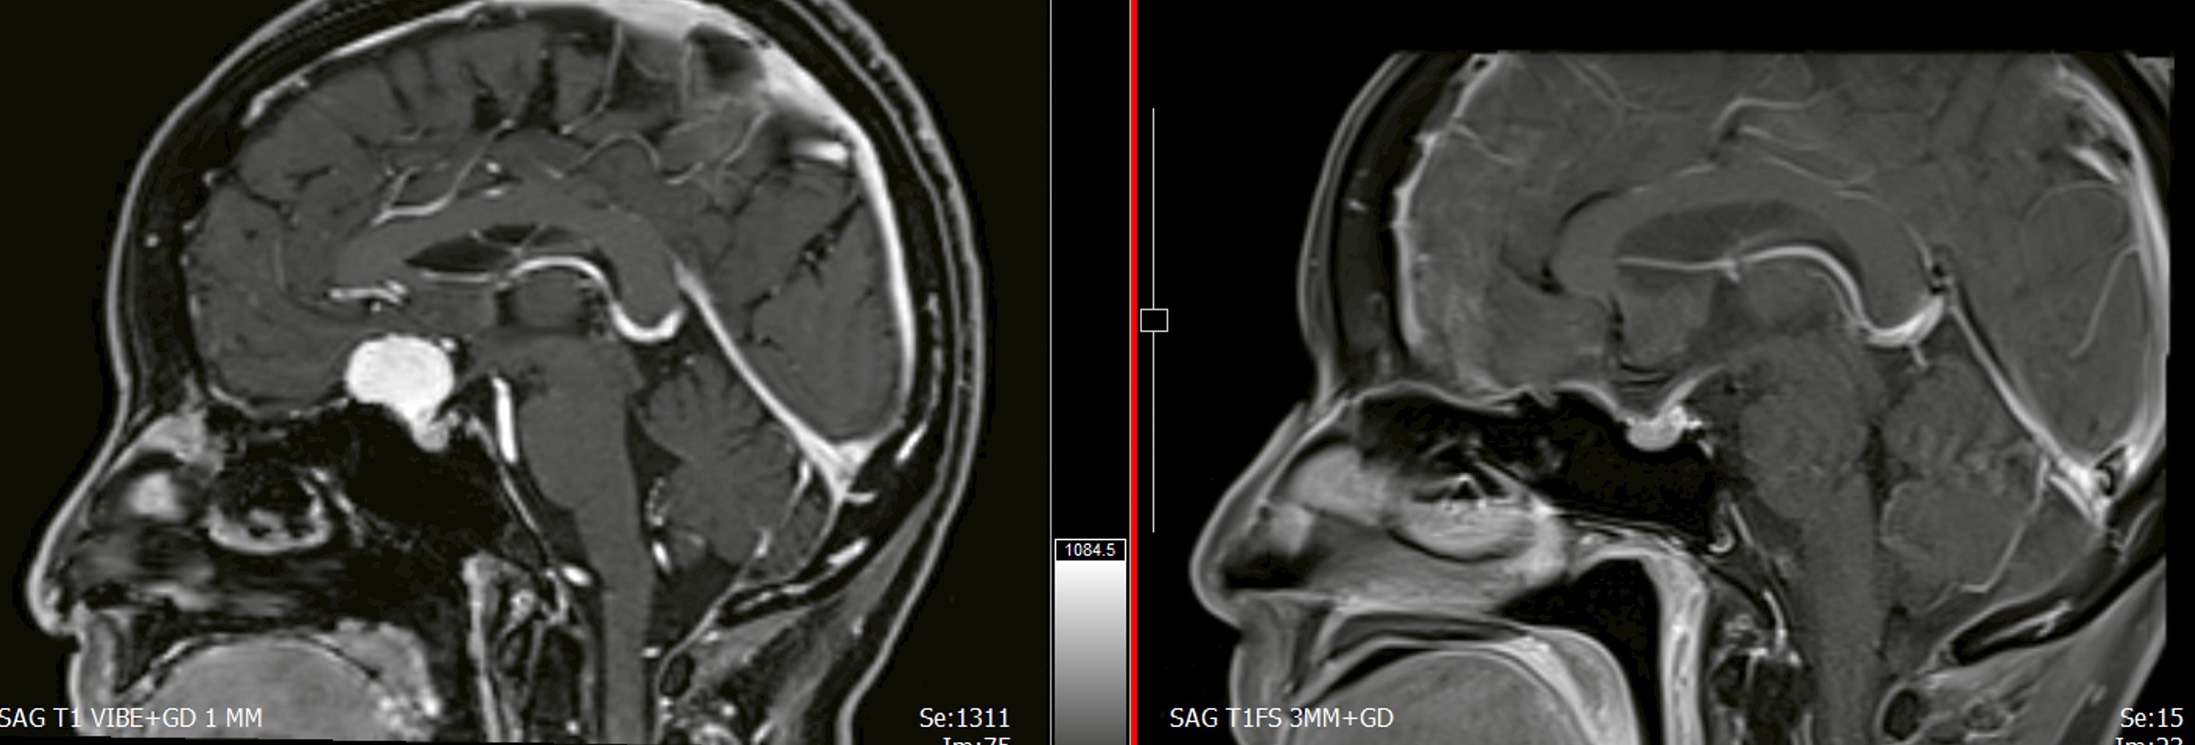

โดย นพ.จอนาตัน อรัญ ตั้งศรีวิมล ศัลยแพทย์ระบบประสาท ได้ดำเนินการผ่าตัดเนื้องอกในสมองบริเวณฐานกะโหลกส่วนหน้า ด้วยเทคนิคการผ่าตัดแผลเล็กผ่านคิ้ว (Eyebrow Keyhole Approach) ซึ่งเป็นเทคนิคการผ่าตัดแบบแผลขนาดเล็กที่มีความแม่นยำสูง

ความพิเศษของการผ่าตัดครั้งนี้ คือ การเข้าถึงตำแหน่งของเนื้องอกผ่านช่องเปิดขนาดเล็กบริเวณคิ้ว จัดเป็นการผ่าตัดแบบแผลเล็ก (Minimally Invasive Surgery) โดยอาศัยกล้อง Microscope และ Endoscope การกล้องส่องตรวจภายในร่วมกับเครื่องนำวิถี ช่วยให้สามารถผ่าตัดได้อย่างแม่นยำ ลดผลกระทบต่อสมองและโครงสร้างสำคัญ ลดระยะเวลาการพักฟื้นในโรงพยาบาล เมื่อเปรียบเทียบกับการผ่าตัดแบบเปิดกะโหลกศีรษะขนาดใหญ่ นับเป็นความก้าวหน้าที่สำคัญของการพัฒนาศัลยกรรมระบบประสาทในประเทศไทย